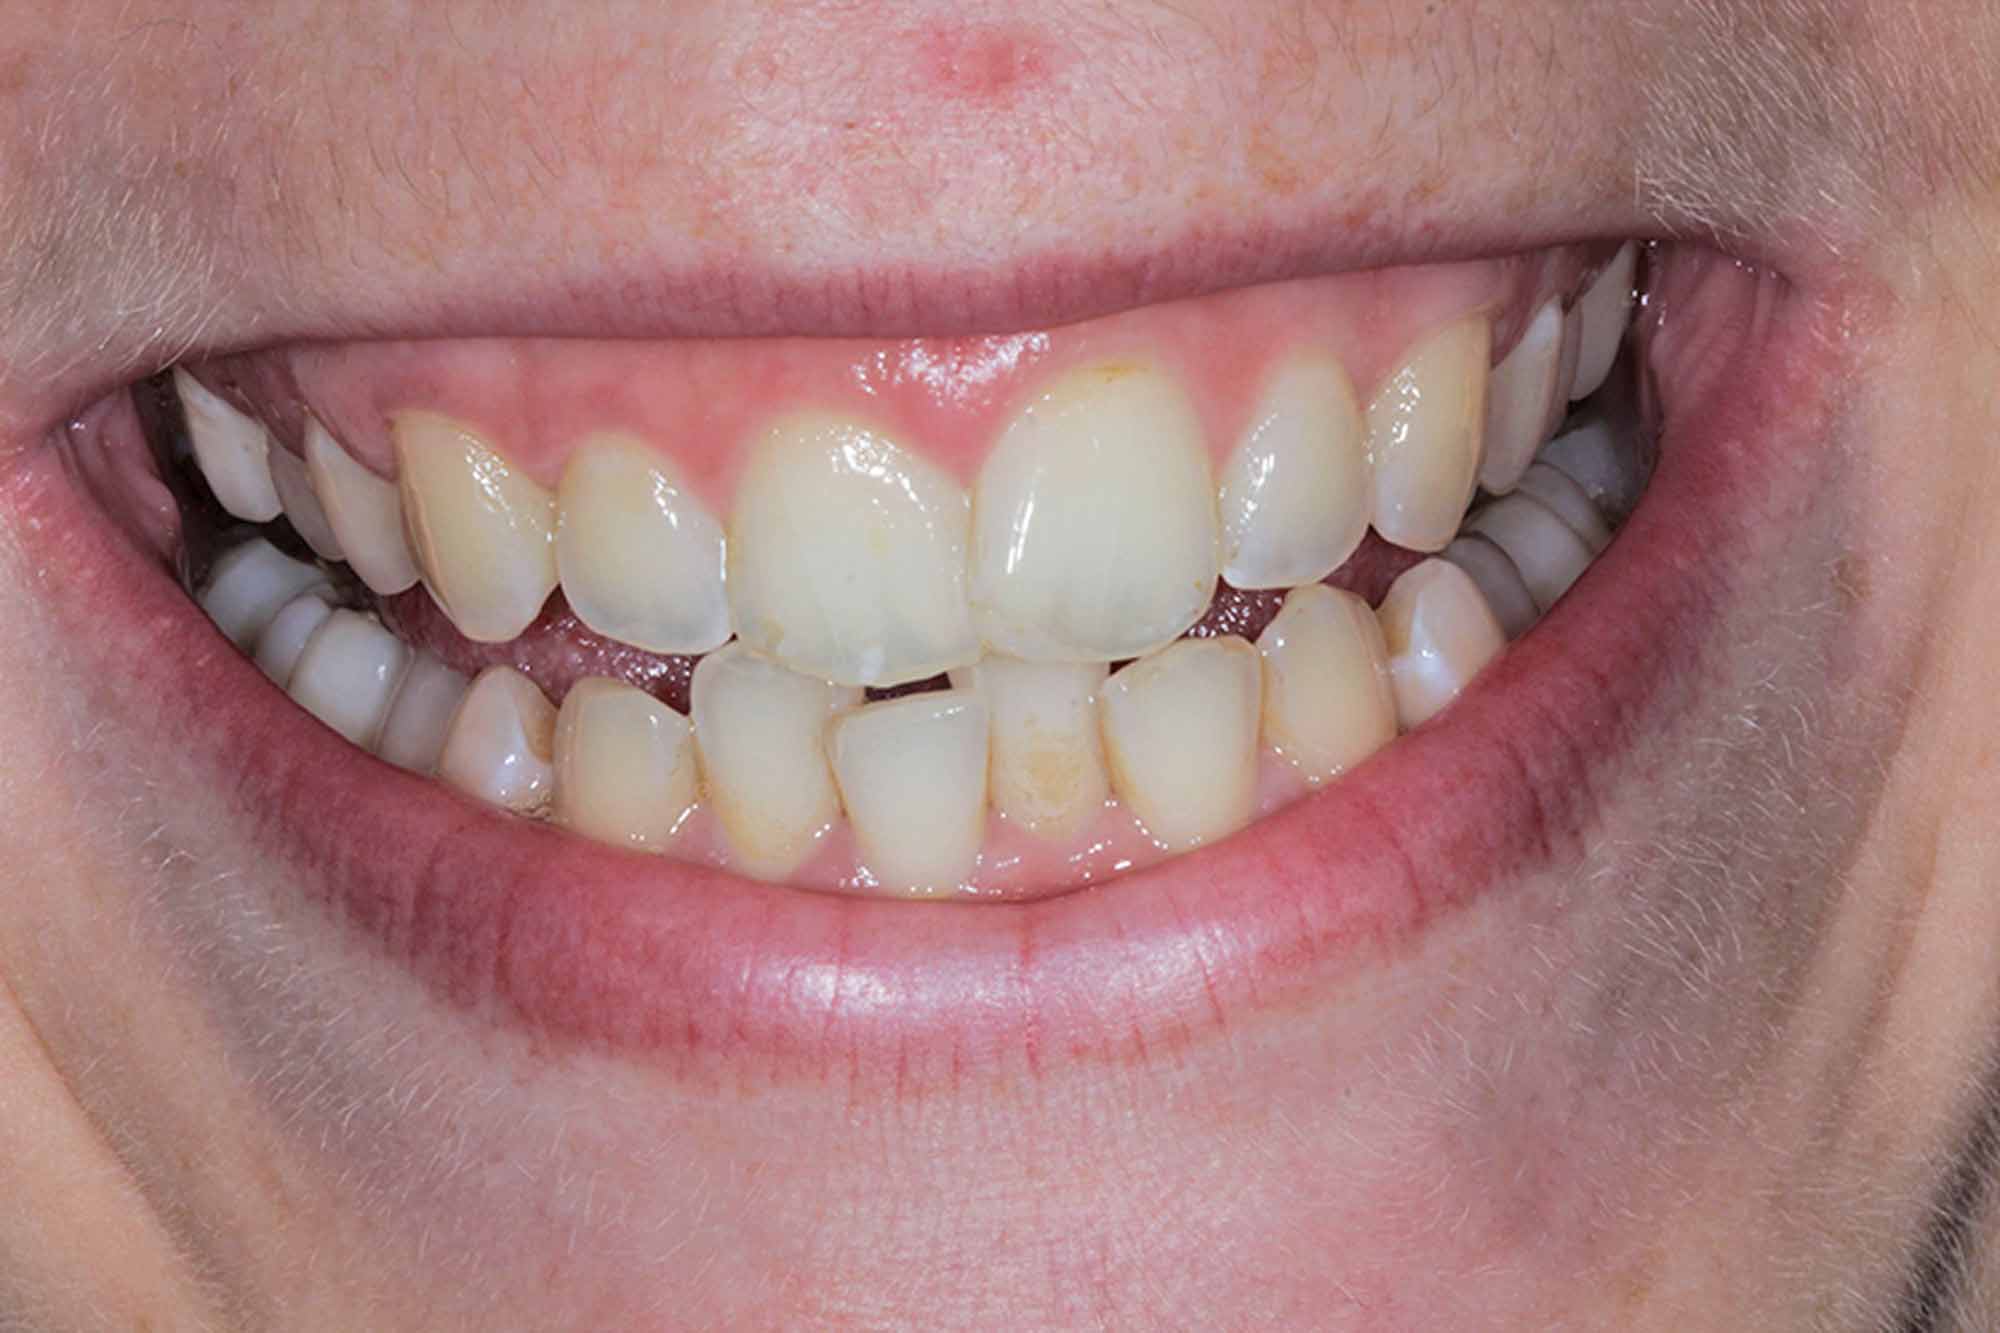

This young female patient presented with misalignment. She wanted a solution that would not only straighten her teeth but also give her the confidence in her smile she’d always wanted.

She was really into her fitness and lifestyle, and felt her current smile did not match her targets or ambitions.

She was looking for a discreet option that she could control and would fit directly into her lifestyle without the need to change it too much.

This made her an ideal Invisalign system candidate.

We started off with her aesthetic smile design, as we always do. She had beautiful smile proportions and the potential for perfection was certainly there as we concentrated on matching her gingival margins, widening her buccal corridors and accepting that incisal tooth wear had certainly taken place with some of the edges.